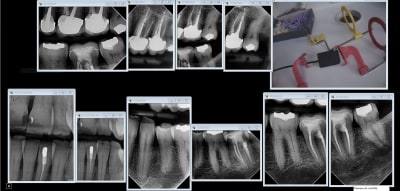

Capteur RVG (filaire) sans hésitation. Moins cher, gain de temps, meilleure qualité d'image et meilleure ergonomie avec les angulateurs Xcp-Ora.

C'est donc un souci d' utilisation. Aucun saignement et des radios j'en fais un stock jamais eu de problème. J'ai eu 1 systèmes à plaques ( CS 7500) l'encombrement moindre n'apporte pas grand chose en plus par contre perte de qualité, et chronophage du fait des pochettes. Je ne m'en servais que pour des bite wings et même pour ça j'ai jeté l'éponge.

Tiens status meilleur rapport qualité - prix capteur taille 2 isensor woodpecker 1500 balles camera MD960 150 balles. Qui dit mieux ?

sinon avec le film chez les jeunes tu peux faire ca, pour le depistage des caries:

Tu peux faire ça aussi.